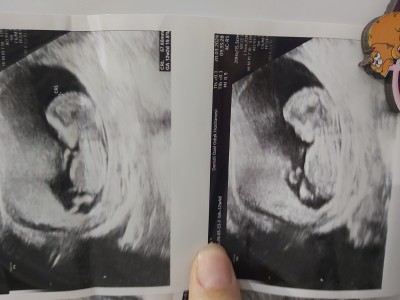

Kız.erkek takıntım yok sadece keyfine merak sizce anlayan varmi

Gebelik haftası 13

Erkek bu bebek kesin

%99 Erkek  maşallah<3

Kız gibi sağlıkla kucağınıza alın